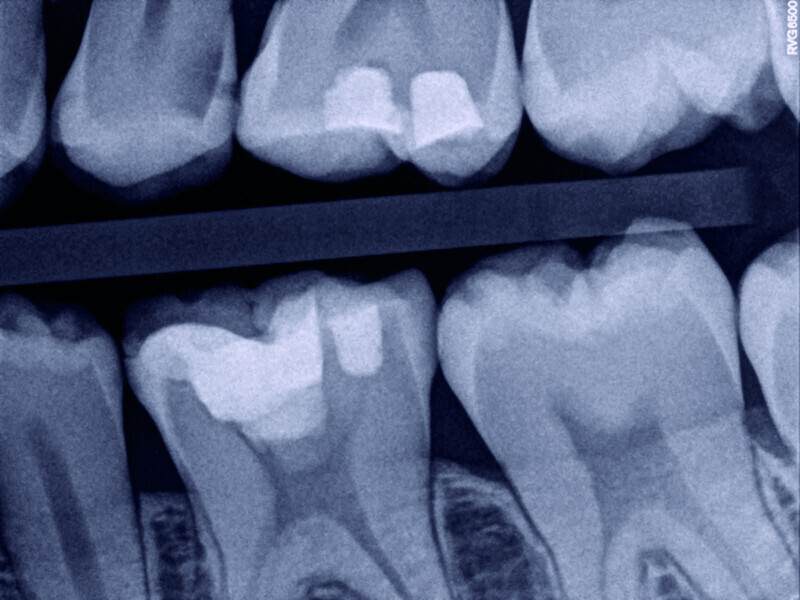

Direct pulp capping as a conservative procedure to maintain pulp vitality